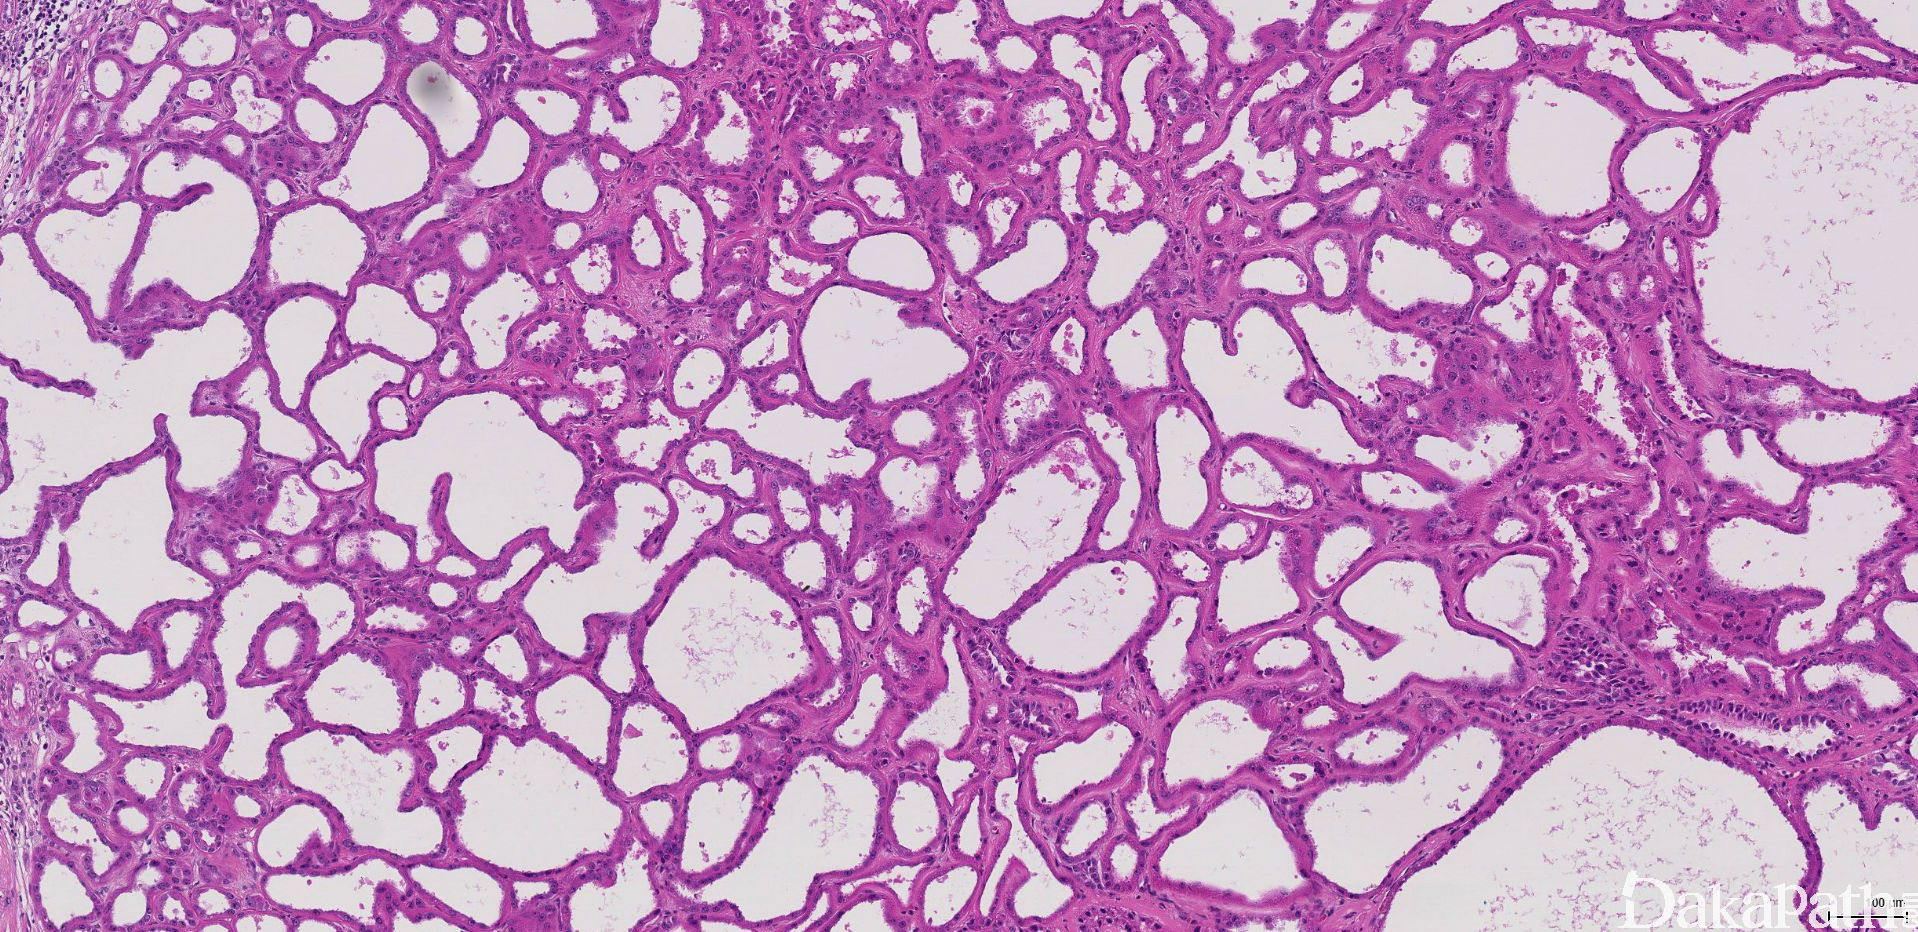

低倍镜下完全由小到中等大的小管和较大的囊肿组成(图 1);被覆瘤细胞单层排列,呈扁平、立方状到柱状、鞋钉样不等(图 2)。管腔或囊腔内容物空,有时可见浅染的嗜酸性分泌物或出血。

瘤细胞胞浆丰富嗜酸性,核圆形或不规则,常见较明显的核仁(ISUP 核分级:3 级,图 3)。

小管或囊肿之间为薄壁的少细胞纤维性间质,一般无炎症浸润或水肿变性。